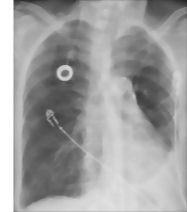

Search Strategy: Pleural Spaces and Diaphragm

Labeled-Cochard Imaging 1E Radiographs